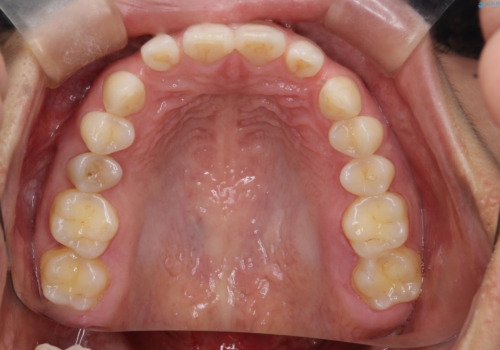

【空隙歯列】ワイヤー矯正で短期間に治療を終えたい

- 歯と歯の間に隙間があることを主訴に来院されました。

短期間での治療終了を希望され、ワイヤー矯正にて治療を行い1年ほどで治療を終了しております。

下顎前歯は矯正後補綴治療を行なっております。

期間や仕上がりで大変満足していただきました。